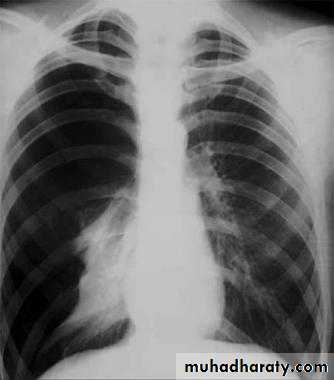

X-ray of pleural effusion

Massive right effusion